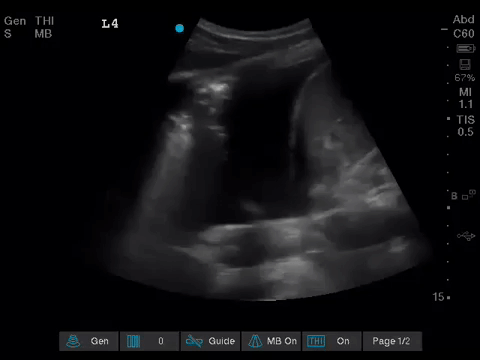

The POCUS team was asked to specifically to assess her lungs to help determine the cause of her dramatically increased oxygen requirements.

Before giving their clinical interpretation of the LUS findings, the POCUS team also scanned the heart and vasculature to obtain a more complete picture.

1. When scanning the lungs, a comprehensive, bilateral lung scan is far superior to a single clip; as this will offer more information and permit an interpretation based on the overall pattern of findings. Had this patient only had the R1 area scanned, for example, we may have reached the erroneous conclusion that her hypoxemia was likely due to pulmonary edema.